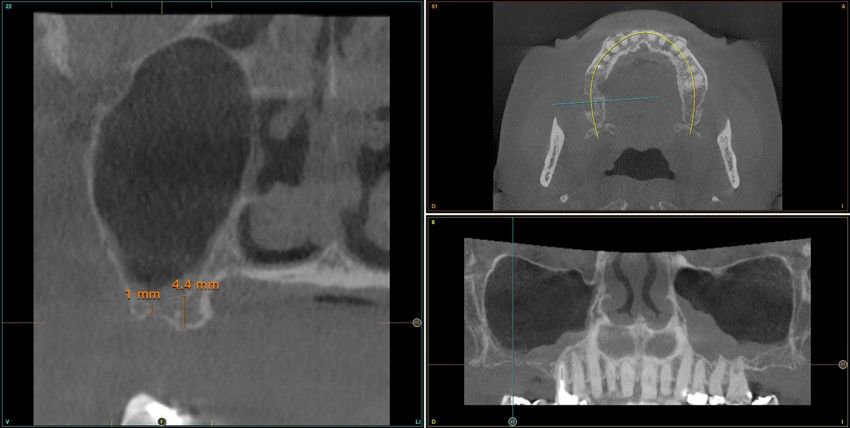

Resultados. Fueron reclutados 13 pacientes en los que se insertaron 30 implantes. Una vez insertados y cargados los implantes, la altura media final fue de 9,68 mm (+/- 2,66), lo que supone una ganancia promedio de 5 mm. A los 10 años, se observó una disminución media de la altura ósea ganada en los implantes en conjunto de 0, 29 mm (+/- 0,77). La media de la pérdida ósea mesial fue de 0,73 mm (+/- 0,75 mm) y la media de la pérdida ósea distal fue de 0,98 mm (+/- 1,2 mm). La supervivencia fue del 100%.

Results.Thirteen patients were recruited and 30 implants were inserted. Once the implants were inserted and loaded, the mean final height was 9.68 mm (+/- 2.66), which represents an average gain of 5 mm. At 10 years, there was a mean decrease in the overall bone height gain of the implants of 0.29 mm (+/- 0.77). The mean mesial bone loss was 0.73 mm (+/- 0.75 mm) and the mean distal bone loss was 0.98 mm (+/- 1.2 mm). Survival was 100%.

Nuestro grupo de estudio modifica esta técnica de elevación transcrestal utilizando para el acceso unas fresas de corte frontal que permiten eliminar la cortical inferior del seno con lentitud sin dañar la membrana de Schneider, eliminándose los osteotomos y el malestar que genera su accionamiento mediante el martillo6-7. Inicialmente el procedimiento fue concebido para ser empleado con material de injerto al igual que el abordaje convencional, pero posteriormente se presentaron variaciones del procedimiento donde se insertaban los implantes sin injerto, utilizándose el propio implante como mantenedor de espacio entre la membrana de Schneider y la cavidad creada entre la membrana y la cresta, permitiendo que esta cavidad no se colapsase y posteriormente fuera colonizada por nuevo hueso7-11.

Los senos tratados con la técnica de elevación transcrestal sin material de relleno muestran un incremento de entre 2,5 mm12,13 hasta 4.4 mm14,15 en la altura ósea lograda sobre el ápice y una supervivencia de los implantes que se sitúa entre un 94 y un 100%16-17. En este trabajo se presenta un estudio retrospectivo donde se ha evaluado la inserción de implantes extracortos (5,5 y 6,5 mm) en zonas posteriores maxilares mediante la técnica de elevación de seno transcrestal con la fresa de ataque frontal sin la utilización de material de injerto, con un tiempo de seguimiento de 10 años para poder objetivar el comportamiento de los implantes a largo plazo y de la técnica empleada.